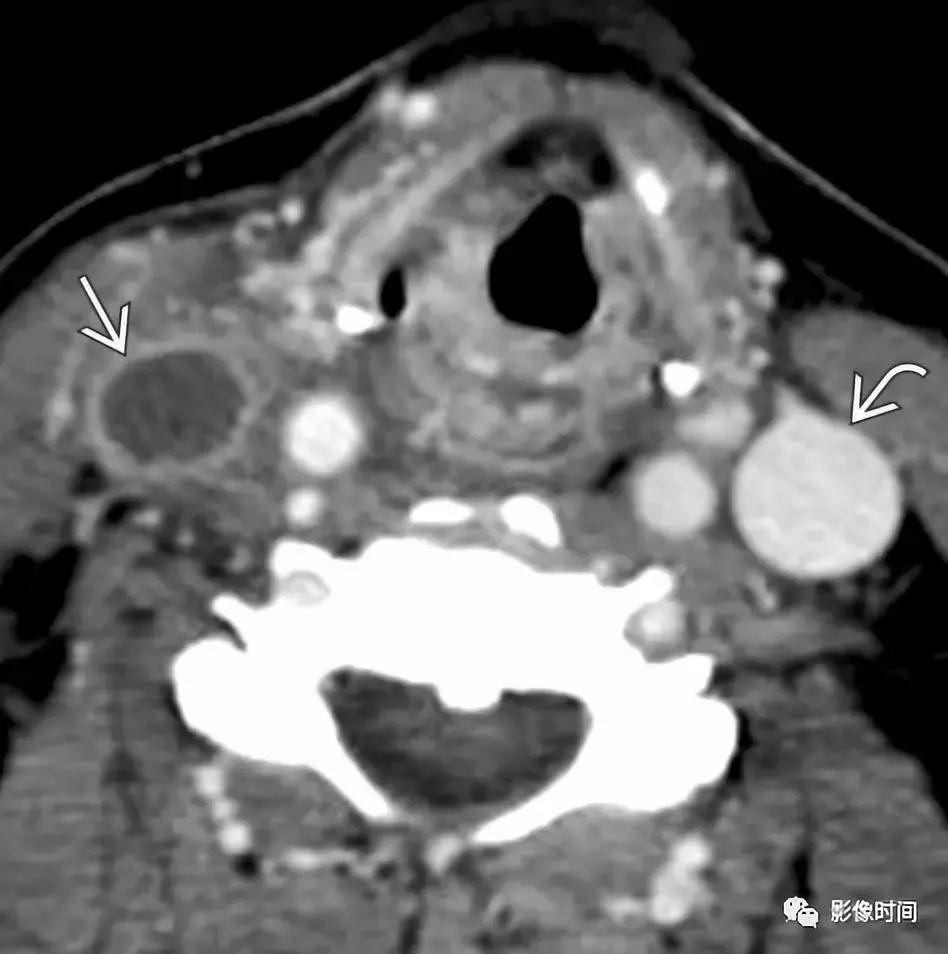

10.淋巴瘤:霍奇金淋巴瘤和非霍奇金淋巴瘤常累及头颈部,影像检查无法将两者区分开。非霍奇金淋巴瘤多见,80-85% 为弥漫大 B 细胞淋巴瘤。患者一般出现无痛性头颈部肿块,伴发烧,体重减轻,盗汗要想到淋巴瘤的可能性。CT 或 MRI 上,淋巴瘤可以单发或多发,多发病灶可见相互融合,常常推挤或包饶周围结构,增强扫描呈不同程度的强化,重要一点:淋巴瘤包饶血管,但不会导致血管管腔狭窄,这种特征有助于和其他疾病区分。虽然 CT 是淋巴瘤初步评估和分期的主要标准,但它只提供结构信息,正电子发射断层显像 (PET) 在淋巴瘤中的作用越来越大,因为可以反映其功能。PET 是评估淋巴瘤治疗的反应以及在治疗后发现残余或复发的关键。

轴位 T1WI+C 显示不均匀强化肿块,完全包裹左侧颈内 (LIC) 和颈外动脉 (LEC)。注意左侧颈内动脉的管腔与右侧颈内动脉 (RIC) 的管径一致。

轴位增强 CT 显示双侧舌骨上颈部多发淋巴瘤,不均匀强化,没有坏死。